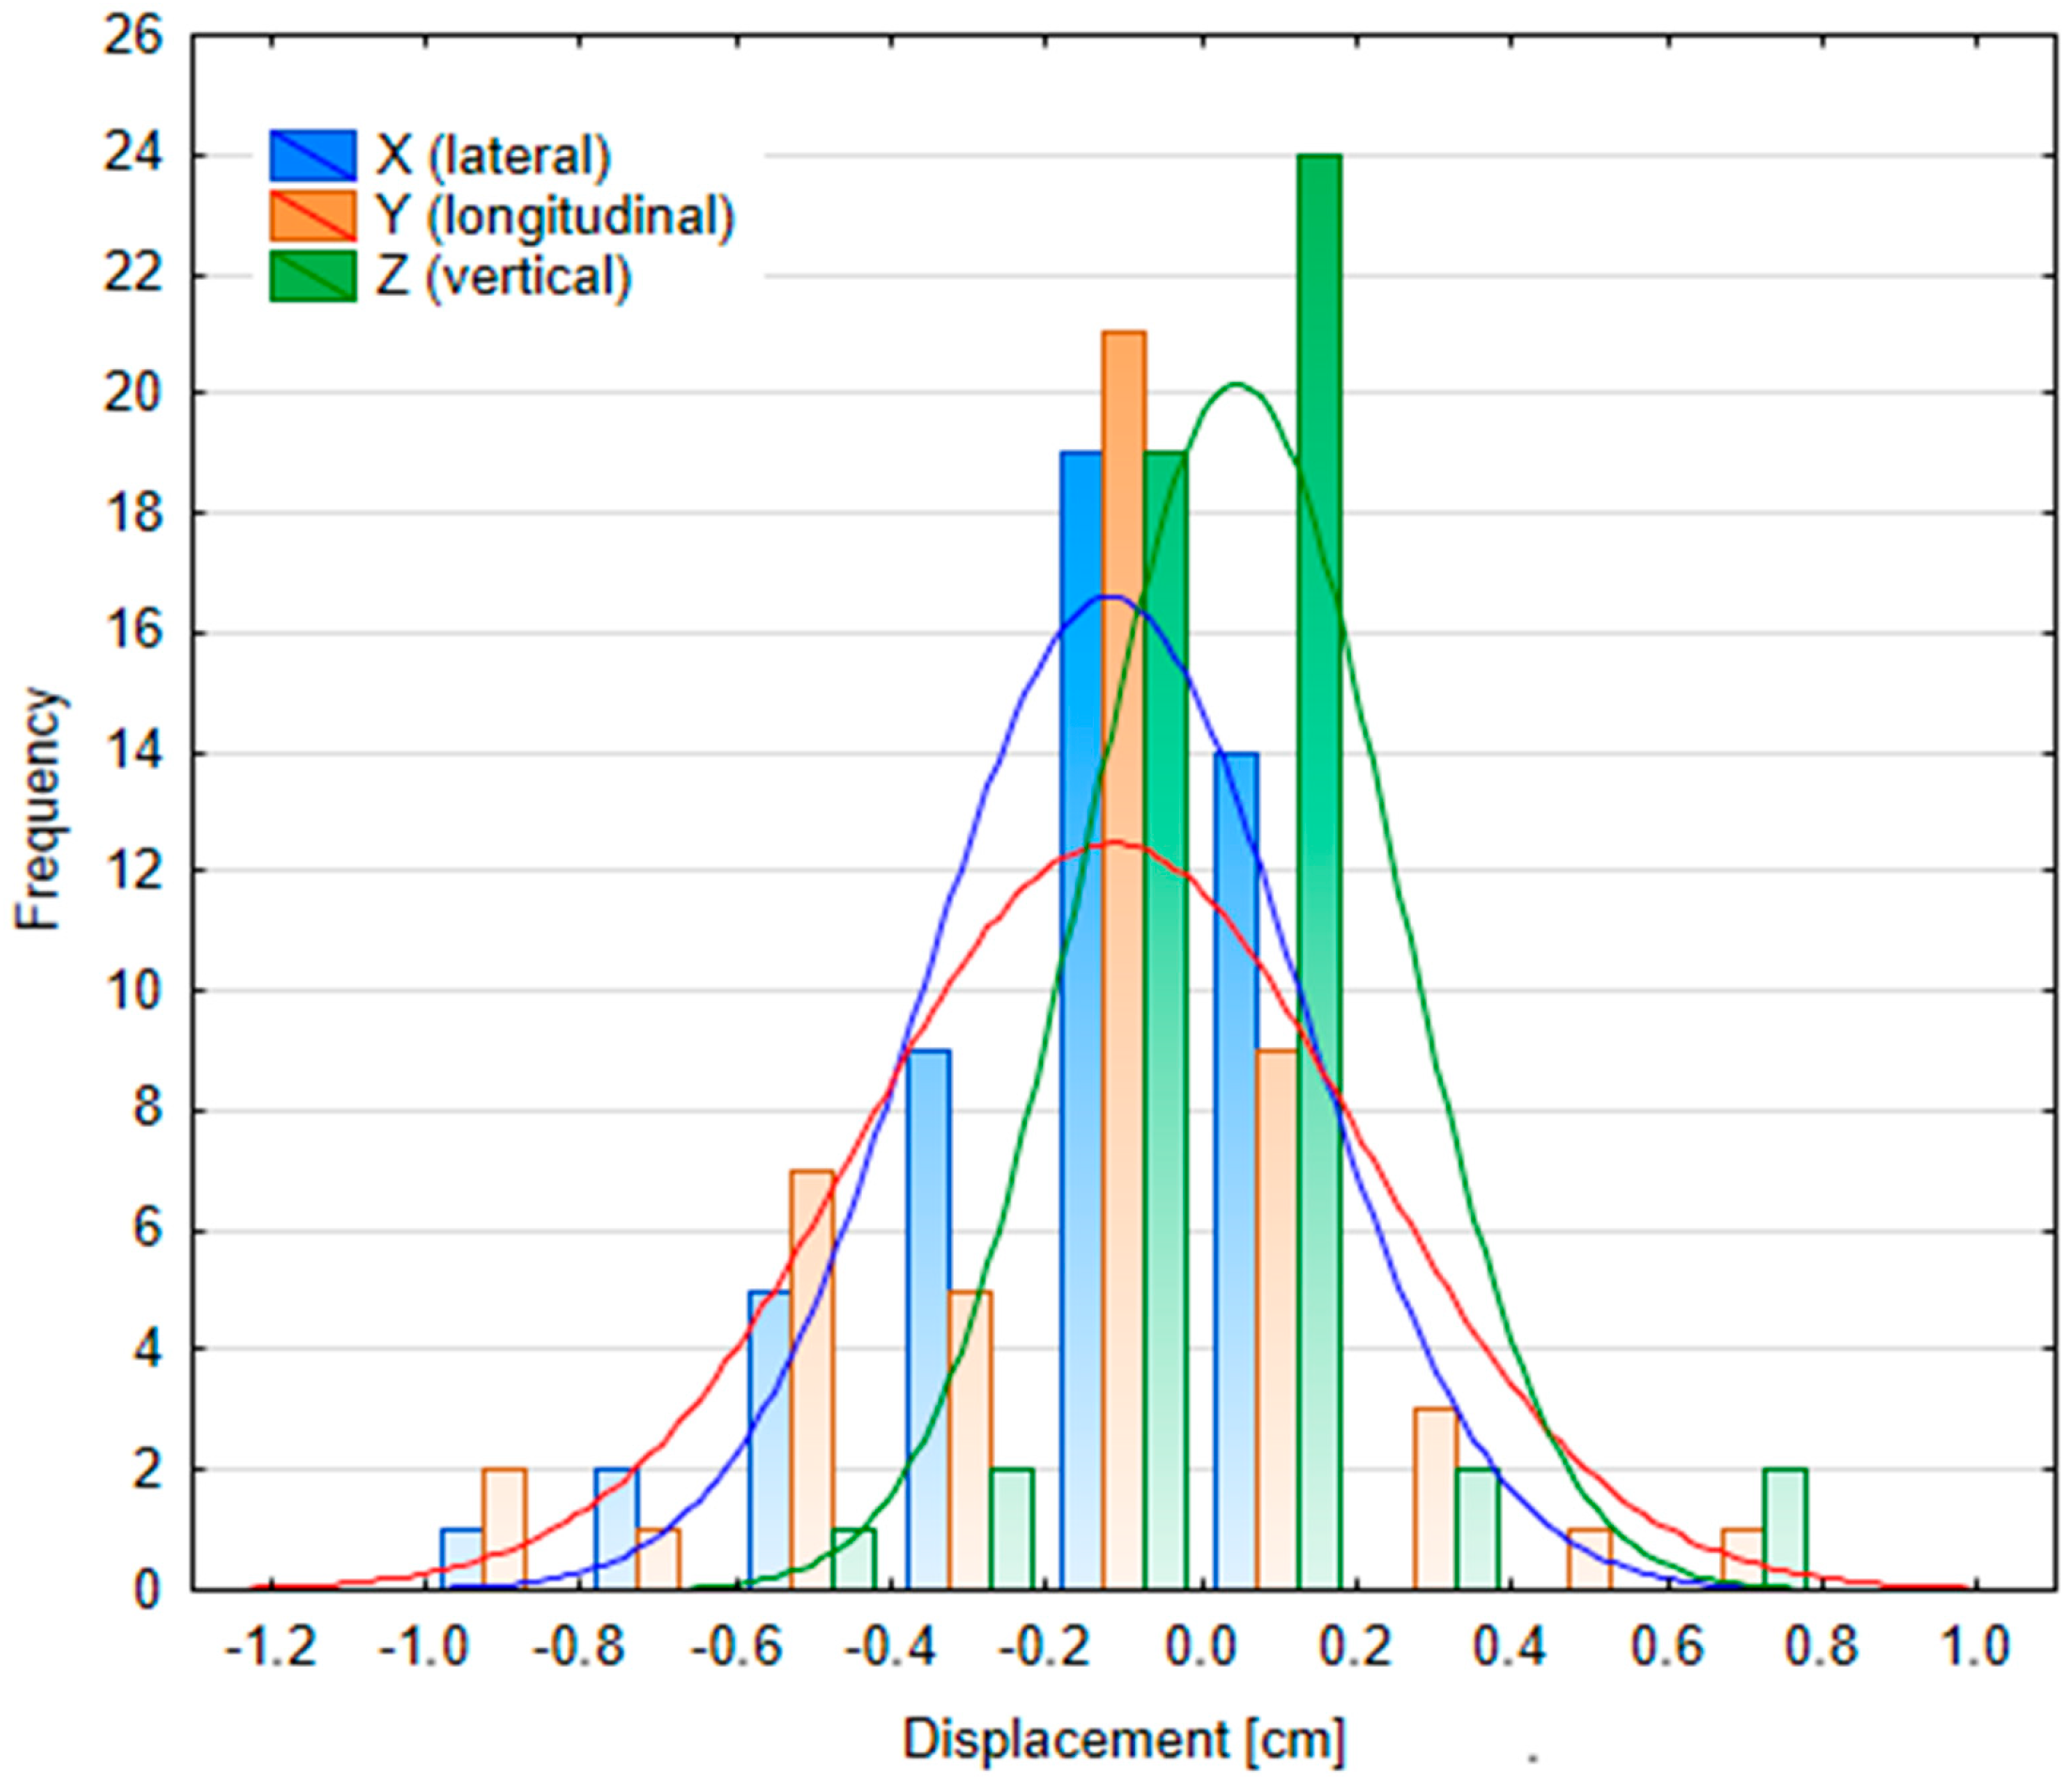

3.2.2. Patient Position Variability

| Table Shift Coordinates | Median kV Portal Imaging Setup Error | Median kV Portal Imaging DIBH Reproducibility | ||||

|---|---|---|---|---|---|---|

| Male (n = 45) | Female (n = 38) | p-Value | Male (n = 17) | Female (n = 33) | p-Value | |

| X (lateral) [cm] | 0 (−0.06; 0.10) | −0.14 (−0.30; 0) | p < 0.05 | 0 (−0.06; 0.03) | −0.09 (−0.34; 0) | p < 0.05 |

| Y (longitudinal) [cm] | 0.02 (−0.14; 0.24) | −0.03 (−0.34; 0.12) | p = 0.16 | 0 (−0.15; 0.06) | −0.07 (−0.45; 0) | p = 0.13 |

| Z (vertical) [cm] | 0 (−0.06; 0.11) | 0.01 (−0.06; 0.12) | p = 0.74 | 0.05 (−0.1; 0.09) | 0.02 (0; 0.12) | p = 0.39 |

| MAG (magnitude) [cm] | 0.34 (0.16; 0.43) | 0.33 (0.17; 0.68) | p = 0.18 | 0 (0; 0.08) | 0 (0; 0.26) | p = 0.06 |

| ROT [°] | 0 (−0.2; 0.4) | 0.65 (0; 1.5) | p < 0.05 | 0 (−0.2; 0.3) | 0.5 (0; 1.5) | p < 0.05 |

| PITCH [°] | −0.31 (−0.93; 0) | −0.05 (−0.3; 0.5) | p < 0.05 | −0.27 (−0.5; 0) | 0 (−0.21; 0.07) | p = 0.11 |

| ROLL [°] | 0 (0; 0) | 0 (0; 0) | p = 0.09 | 0 (0; 0) | 0 (0; 0) | p = 0.43 |

| Tolerances Within | kV Portal Imaging Setup Error (Interfractional, n = 91) | kV Portal Imaging DIBH Reproducibility (Intrafractional, n = 48) | ||||

|---|---|---|---|---|---|---|

| X | Y | Z | X | Y | Z | |

| 1 mm | 45.1% | 34.1% | 50.5% | 45.8% | 41.7% | 56.3% |

| 2 mm | 63.7% | 46.2% | 80.2% | 64.6% | 56.3% | 85.4% |

| 3 mm | 82.4% | 58.2% | 87.9% | 75.0% | 66.7% | 91.7% |

| 4 mm | 90.1% | 74.7% | 93.4% | 83.3% | 75.0% | 93.8% |

| 5 mm | 96.7% | 82.4% | 97.8% | 93.8% | 85.4% | 93.8% |